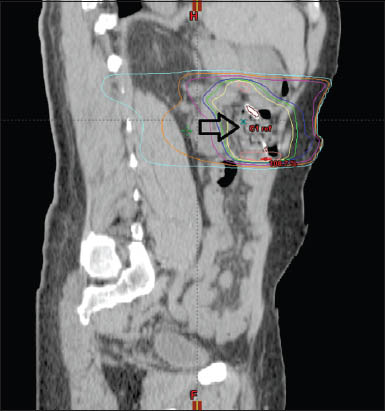

Figure 3

Radiation therapy planning; arrow shows endoscopically placed resolution clips as metallic densities on computed tomography scan

A 72-year-old man was diagnosed with stage IAE extraintestinal MCL in 2008 and was treated with three cycles of rituximab, cyclophosphamide, doxorubicin, vincristine and prednisone (R-CHOP) achieving a complete response. He was subsequently placed on rituximab maintenance therapy for two years with intent to augment overall survival. Repeat PET-CT scan in January 2012 showed a single focus of uptake (SUV 5.3) in the descending colon. Colonoscopy confirmed a large protruding erythematous hard mass (Fig. 1A) and biopsy was positive for recurrent MCL (Fig. 2A). The patient was treated with four cycles of bendamustine and rituximab, which he completed in July 2012. A repeat PET-CT in August 2012 showed no evidence of disease. Colonoscopy revealed a substantial decrease in tumor volume (Fig. 1B) with histology positive for persistent MCL confirming only partial tumor response (Fig. 2B). Additional systemic chemotherapy was deferred by the patient and decision was made to proceed with external beam salvage RT. Repeat colonoscopy was performed and the residual tumor area was easily identified by mucosal irregularities and previously placed ink tattoo. Four hemostatic resolution clips (Boston Scientific, Massachusetts, USA) were endoscopically placed to mark the superior, inferior, lateral and medial extent of the tumor, in a “shooting target” fashion to facilitate in planned directed external beam RT (Fig. 1C) and to minimize the radius of toxic radiation exposure to the adjacent normal tissue (Fig. 3, arrow). Patient underwent uneventful RT with twenty targeted fractions and total radiation dose of 36 Gy without side effects or adverse events. Follow up colonoscopy with biopsy 6 months after RT showed no endoscopic or histologic evidence of residual disease or toxicity (Fig. 1D). Fourteen months after completion of RT, the patient remains in complete remission.

Our case is a novel description of endoscopic utilization of fiducial markers in the colon for treatment of MCL using RT. While anecdotal use of metal clips as a guide in RT planning for patients suffering from lung and esophageal cancers has been described, this “targeted” approach has not yet been applied for intestinal tumors [9-11]. Given high predilection of MCL to the gut, colonoscopy may be essential in post-treatment assessment and additional guidance, including radiation planning. Given the close proximity of the colon to other intra-abdominal structures and its regional mobility, RT planning is challenging. Use of endoscopically placed markers (metallic clips) may offer advantage in calculating exact field and volume prior to application of toxic radiation. Retrospective tumor volume and radiation dose analysis in our patient showed “clip-free” standard approach would have overestimated planning and gross tumor volume (GTV) for a total of 717 mL. With the endoscopically placed clips as markers, GTV was calculated at 268 mL - effectively reducing the volume by 63% and thus allowing for more targeted radiation delivery. This approach avoided excess toxicity to the surrounding organs and tremendously reduced risk of radiation-related morbidity. In fact, our patient tolerated RT well, without side effects and a post-treatment colonoscopy confirmed resolution of lymphoma and absence of significant radiation injury to the adjacent tissue.